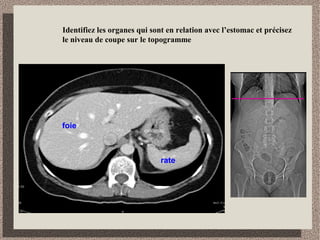

Identifiez les organes qui sont en relation avec l’estomac et précisez

le niveau de coupe sur le topogramme

foie

rate

estomac